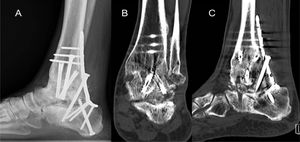

Caso clínicoSe reporta el caso de un paciente de sexo masculino, de 42 años, sano, con antecedente de artrosis postraumática de tobillo izquierdo por luxofractura expuesta de tobillo el 2021. Fue manejada con una artrodesis tibiotalar el 2022, requiriendo una revisión a los dos meses. Dos meses después de la primera revisión se realizó una artrodesis subtalar que a los 10 meses de evolución también requirió una revisión por no unión (figura 1). El paciente no aporta mayores antecedentes sobre sus cirugías previas e indicaciones quirúrgicas correspondientes.

Se realizó estudio con exámenes de laboratorio que descarta una infección asociada como causa de no unión. Una tomografía computarizada (TC) de tobillo muestra consolidación adecuada de artrodesis tibio talar y no unión de la artrodesis subtalar, diagnosticándose así la no unión aséptica de la artrodesis subtalar de tobillo izquierdo.

En este contexto se decide realizar una nueva revisión. Para esto se realiza artrodesis de revisión tibiocalcánea donde se aumenta estabilidad y rigidez del constructo con placa posterior tibiocalcánea con tornillo de compresión interfragmentaria a través de la placa+tornillo retrógrado calcáneo talar. Se realiza resección de pseudoartrosis, tejido óseo no vital y preparación de remanente de superficie articular subtalar posterior+agregación de autoinjerto de tibia proximal y aloinjerto de cresta ilíaca y augmentación con plasma rico en plaquetas (PRP) en julio de 2024 (figura 2). La línea de tiempo del caso clínico se detalla en la figura 3.